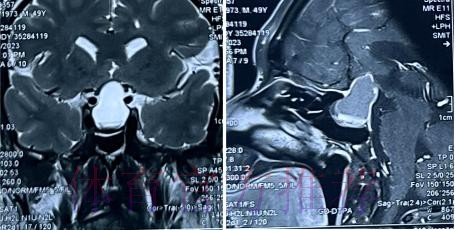

在高速对抗的现代足球里 现场肉眼和赛后情绪往往会放大对伤情的判断 一名球员倒地呻吟或无法坚持比赛 很容易被解读为韧带断裂 或肌肉严重撕裂 但真正决定恢复周期的关键因素 通常要到核磁共振检查之后才会明朗 因为核磁能在较早阶段清晰显示软组织 肌肉 韧带以及骨结构的微小损伤情况 对伤情做出更接近真相的分级判断 塞巴略斯此次就是典型案例 初步观感可能让人联想到更严重的伤病 但核磁提示伤情相对可控 没有出现完全断裂或大面积撕裂 也就意味着他不需要漫长的康复旅程 只要遵循医学建议 科学负荷管理 就有机会用较短的时间重新回到训练场和比赛中

塞巴略斯这一类型的技术中场 通常触球频繁 变向急促 需要大范围穿插跑动 在这种比赛习惯下 肌肉和韧带承受的累积负荷极高 尤其在密集赛程和高压对抗中 任何一次小小的失衡或强硬对抗 都可能放大为潜在伤病 因此外界对他伤情格外敏感 并非夸张反应 而是基于过往大量案例得出的经验判断 从厄德高 德布劳内 再到其他同类型中场 很多球员都在职业生涯某个阶段与伤病长期共存 一旦错过最佳治疗和恢复窗口 轻伤有可能拖成旧患 进而影响球员的爆发力 节奏控制能力乃至职业寿命 在这一背景下 经核磁共振检查确认 塞巴略斯伤情没有预期严重 其实反映的是球队在医疗体系 与负荷管理上的相对成熟 至少在第一时间 做到了科学评估 而不是情绪化处理

足球历史上 不乏因为伤情评估偏差而延误治疗的例子 某些球员在初诊时被认定为普通拉伤 结果因为没有进行完整的核磁共振检查 继续带伤出战 最终发展成严重撕裂 被迫长时间缺阵 从竞技层面来看 一次错误判断 可能直接改写一个赛季的走向 也可能在球员的职业生涯里留下不可逆转的隐患 与这些案例对照 塞巴略斯这次的过程显得更为规范 受伤后迅速接受医学影像检查 医疗团队根据结果评估伤情等级 给出清晰恢复计划 俱乐部层面则通过官方渠道适度释出消息 在 保护隐私与满足公众关切之间 取得平衡 对比之下 可以看出 现代职业俱乐部在伤病管理上的专业程度 已远超十几年前更多依赖经验和肉眼判断的时代 同时也提醒公众 不要被比赛画面中的瞬间表现完全左右 而是学会等待更权威的医学信息